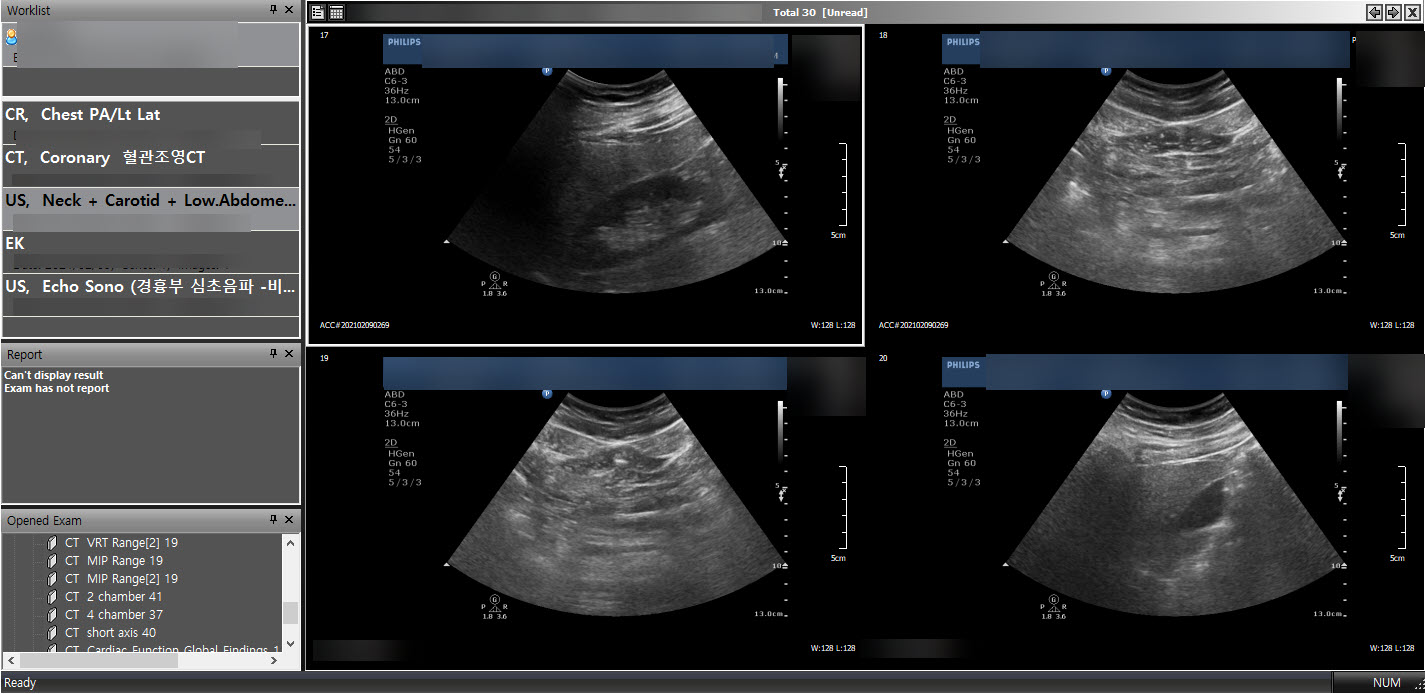

PACS는 CT, MRI와 같은 의료영상장비를 사용하여 촬영된 이미지(DICOM형식)를 저장, 가공, 전송할수있는 시스템이다. 의사는 PACS viewer를 통하여 영상을 판독하고 환자의 상태를 진단할수있다. 다양한 종류의 PACS 뷰어 프로그램이있으며 PacsPlusCV는 PACS 뷰어의 일종이다.

프로그램을 실행하고 의료용 디지털 영상 포맷인 DICOM파일(.dcm)을 불러오기하면 촬영영상 이미지를 확인할수있다.